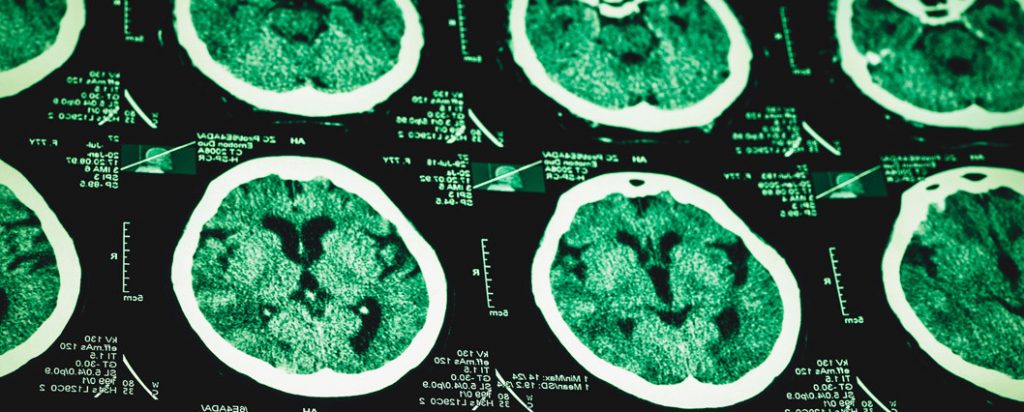

Althealthworks.com reports: Adderall increases dopamine and norepinephrine – the neurotransmitters that help control the brain’s pleasure center and parts of the brain that are responsible for decision making and attention span. Some medical professionals believe that those who have lower levels of both of these neurotransmitters have ADHD.

- permanent brain damage